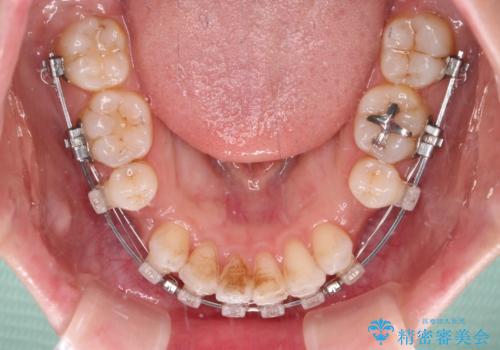

唇が閉じにくい ワイヤー装置での抜歯矯正

- 唇が閉じにくく、上の前歯が下唇に当たって気になるとのことで来院された患者様です。

レントゲン写真での分析結果からは、抜歯矯正をするかどうか悩む境界線上でしたが、主訴が口元の突出感であったため、上下左右の第一小臼歯4本を抜歯して矯正治療を行うこととしました。

上下ともに前歯が少し舌側に傾斜したような仕上がりとなりましたが、口が閉じやすくなったとのことで、患者様には大変満足していただけました。